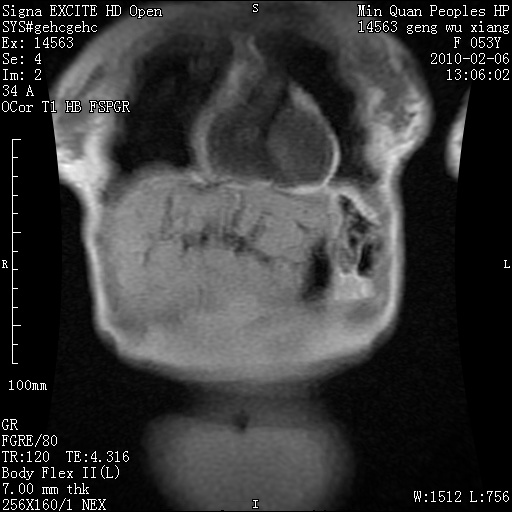

标题: MRI2762:胆道梗阻原因?

f,53y,全身黄染多日。

高位胆道梗阻 胆管癌可能性大

支持 高位胆道梗阻 胆管癌可能性大。